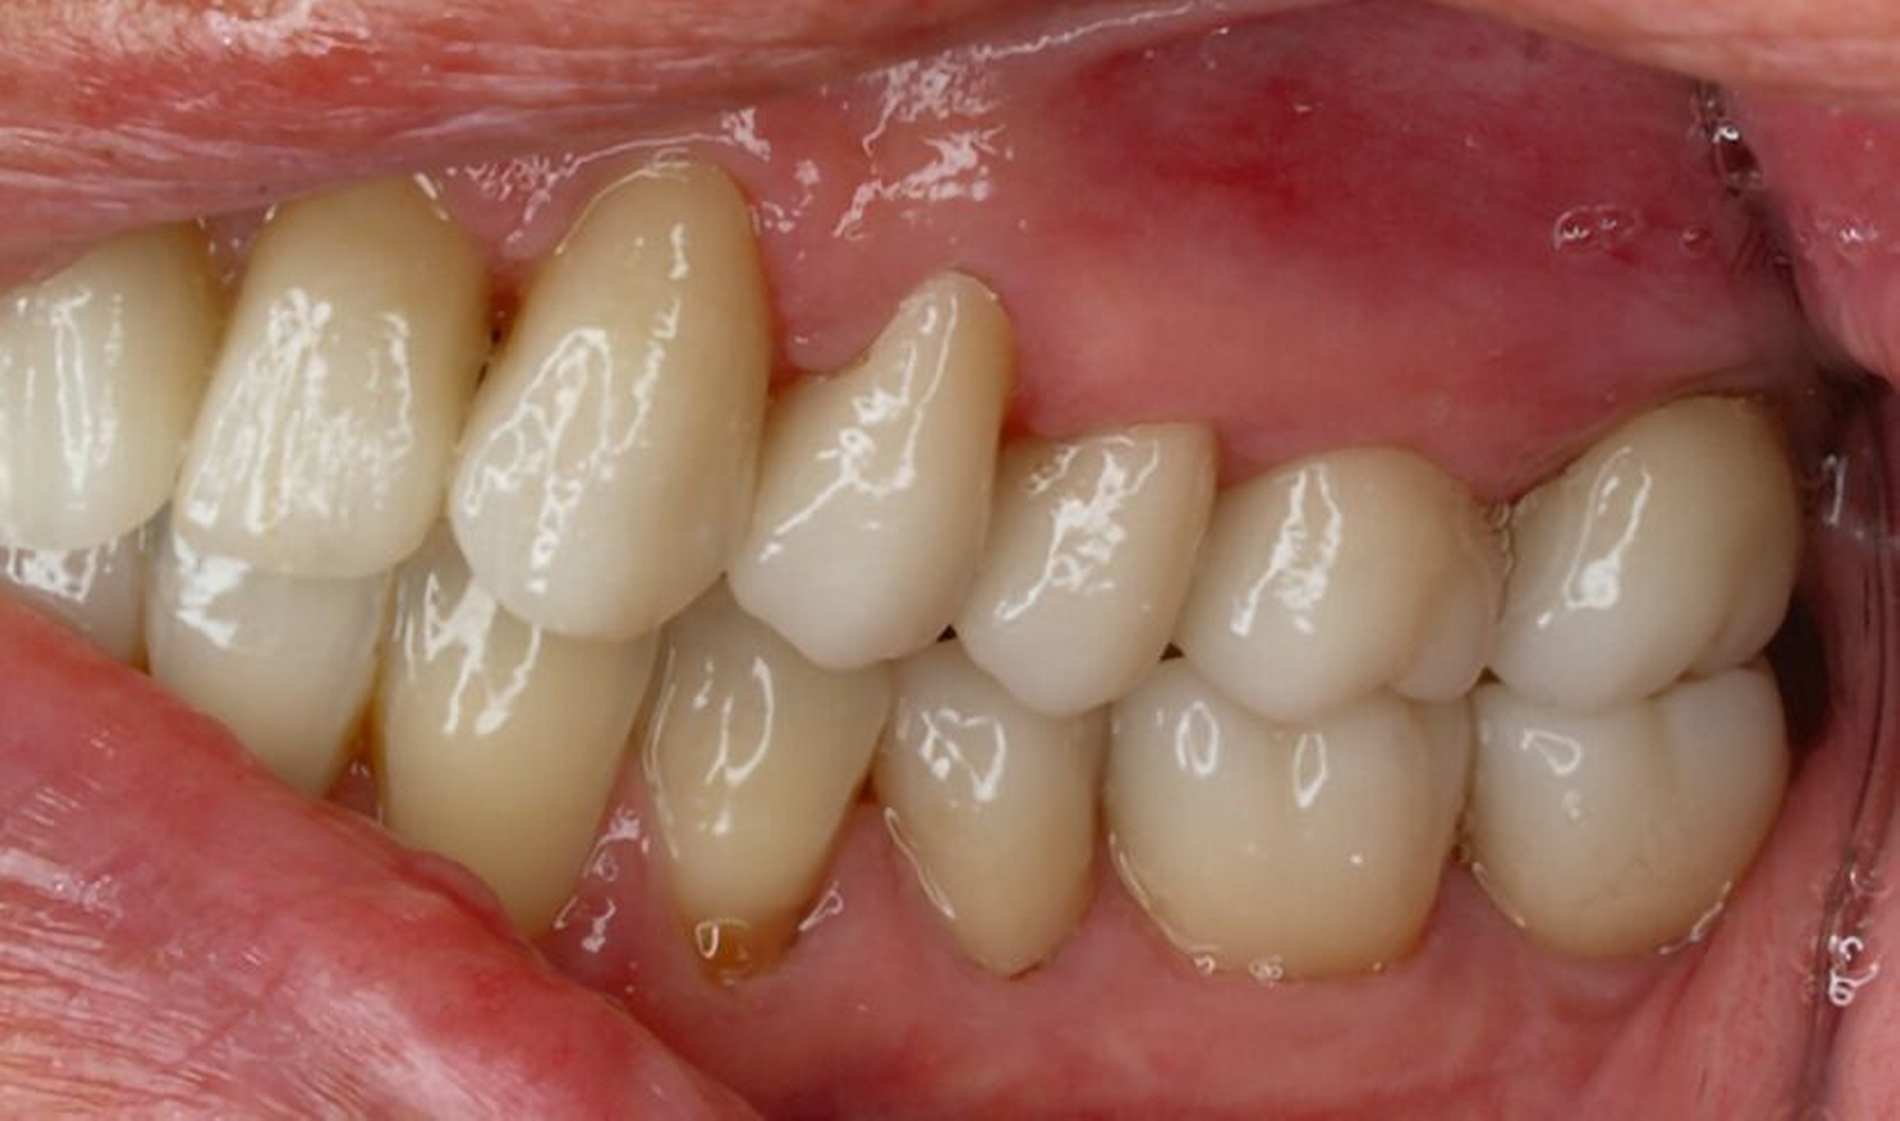

Tabelle 1 zeigt das entsprechende Befundschema mit den Taschentiefen mesial und distal, den Lockerungsgraden und den Sensibilitätsüberprüfungen mittels Kältespray (ViPr). Die Ruheschwebelage wurde mithilfe des Zielinsky-Zirkels auf 2 mm bestimmt. Die Nonokklusion im Seitenzahnbereich konnte auf circa 1,5 mm bemessen werden. Tabelle 2 spiegelt das entsprechende Okklusionsprotokoll wider. Das Okklusionsprofil wird auch in den Abbildungen 3a bis 3c deutlich.

Der festsitzende Zahnersatz wurde im zahntechnischen Labor designt und aufgrund der hohen Zahl der abzuformenden Zähne zunächst aus dem PMMA Telio® CAD (Ivoclar Vivadent) gefräst, um das suffiziente Abschließen der Kronenränder sowie die statische und dynamische Okklusion überprüfen zu können (Abbildungen 8a bis 8c). Danach folgte die Rohbrandanprobe (Abbildung 9). Hierbei konnten noch einmal final Form und Farbe überprüft werden, bevor die Kronen mit einem Glanzbrand schließlich ihre endgültige Gestalt (Abbildung 10) annahmen. Im letzten Schritt wurden die Kronen schließlich mit RelyX™ Unicem 2 (3M™) selbstadhäsiv auf den Stümpfen befestigt. Mit dem Endergebnis war die Patientin hochzufrieden.

Die anschließenden Verlaufskontrollen zeigten klinisch stabile Verhältnisse. Der prothetische Behandlungsaufwand betrug etwa acht Monate inklusive Planung, Begutachtung, Durchführung und Inkorporation des Zahnersatzes. In den Folgeterminen wurde der Patientin noch eine Aufbissschiene für den Unterkiefer eingegliedert, um Schäden durch etwaigen Schlafbruxismus vorzubeugen [Macedo et al., 2007]. Für die Nachsorge empfiehlt sich ein halbjährliches Kontrollintervall. Die erfolgte Okklusionskorrektur im Seitenzahnbereich wird in Abbildung 11 deutlich.